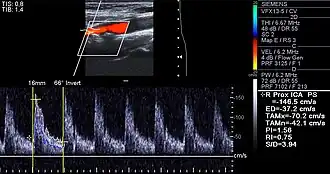

Doppler ultrasound of right internal carotid artery with calcified and non-calcified plaques showing less than 70% stenosis

Lumen stenosis that is greater than 75% was considered the hallmark of clinically significant disease in the past because recurring episodes of angina and abnormalities in stress tests are only detectable at that particular severity of stenosis. However, clinical trials have shown that only about 14% of clinically debilitating events occur at sites with more than 75% stenosis. Most cardiovascular events that involve the sudden rupture of the atheroma plaque do not display any evident luminal narrowing. Thus, greater attention has been focused on "vulnerable plaque" since the late 1990s.[84]

Besides the traditional diagnostic methods such as angiography and stress-testing, other detection techniques have been developed in the past decades for earlier detection of atherosclerotic disease. Some of the detection approaches include anatomical detection and physiological measurement.

Examples of anatomical detection methods include coronary calcium scoring by CT, carotid IMT (intimal media thickness) measurement by ultrasound, and intravascular imaging techniques, such as intravascular ultrasound (IVUS), and intravascular optical coherence tomography (OCT),[85][86] allowing direct visualization of atherosclerotic plaques.